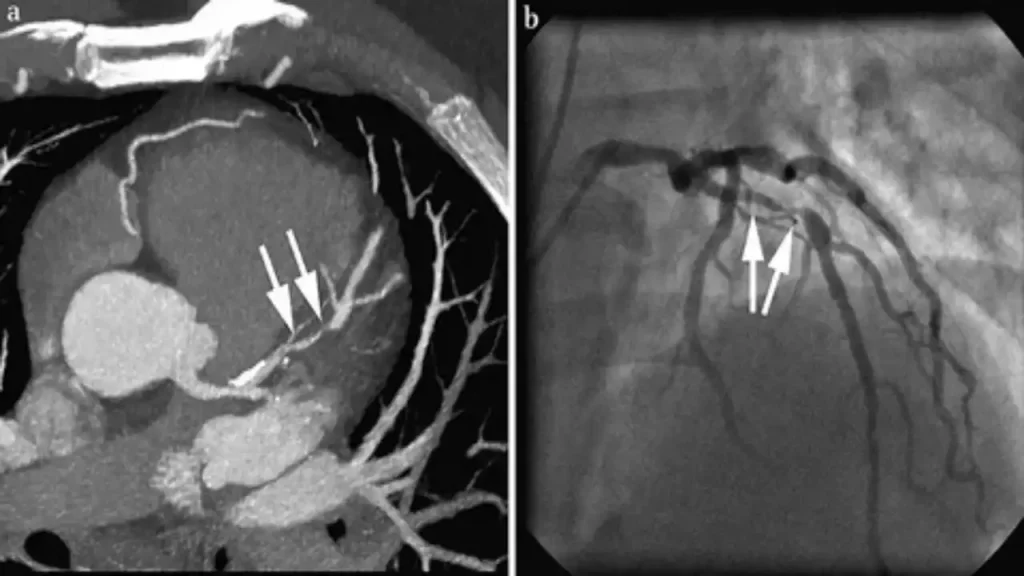

تعریف CT Angio ریه

سیتی آنژیو عروق ریه یا CT Pulmonary Angiography، یک روش تصویربرداری پیشرفته پزشکی است که با استفاده از پرتوهای X و تزریق ماده حاجب (کنتراست) رادیولوژیکی، تصاویر دقیق از رگهای خونی ریهها ارائه میدهد. این تکنیک به پزشکان امکان میدهد ساختار رگهای ریوی را به صورت سهبعدی مشاهده کرده و هرگونه انسداد، لخته خون یا ناهنجاری را با دقت بالا تشخیص دهند. سیتی آنژیو عروق ریه نسبت به روشهای سنتی مانند آنژیوگرافی تهاجمی، غیرتهاجمی و سریعتر است و نیاز به بستری طولانی مدت ندارد.

سیتی آنژیوگرافی ریه یک روش تصویربرداری پیشرفته است که با استفاده از اشعه ایکس و ماده حاجب، جریان خون در عروق ریوی را نمایش میدهد. این روش به پزشکان امکان میدهد تا انسدادها، آمبولیها و سایر اختلالات عروقی را با دقت بالا شناسایی کنند. علاوه بر دقت تشخیصی، سیتی آنژیو عروق ریه به پزشکان کمک میکند درمان مناسب را سریعتر تجویز کنند. با توجه به اهمیت این روش، اطلاع از هزینه سی تی آنژیو عروق ریه برای برنامهریزی مالی و استفاده بهینه از بیمهها ضروری است.